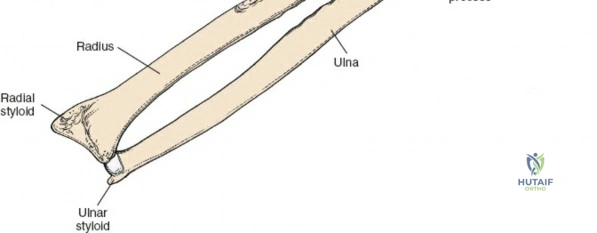

Osteology and Biomechanics of the Proximal Radius

The radius and ulna function together as a highly coordinated articular quadrangle. The proximal radius consists of the radial head, which articulates with the capitellum; the radial neck; and the bicipital tuberosity, which serves as the insertion site for the biceps brachii tendon. The biomechanics of the forearm dictate that the radius rotates around the stationary ulna during pronation and supination. The normal lateral curvature of the radius—the radial bow—is critical for this rotational clearance. Any surgical approach to the proximal radius must allow for the precise restoration of this bow, as even a minor malreduction can lead to profound deficits in forearm rotation.